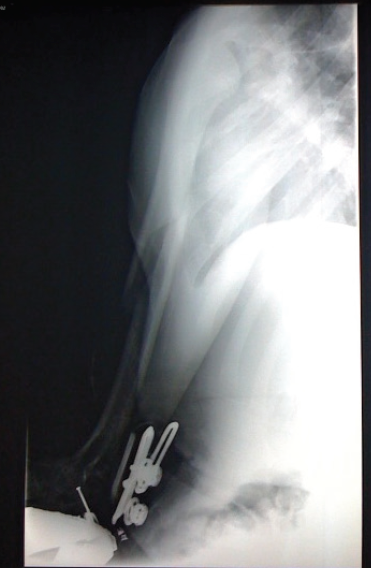

Plain radiographs led to the diagnosis.

ANSWER: Ball-thrower’s fracture

The radiographs revealed ball-thrower’s fracture—an oblique fracture of the right midhumeral shaft, displaced posteriorly and medially.